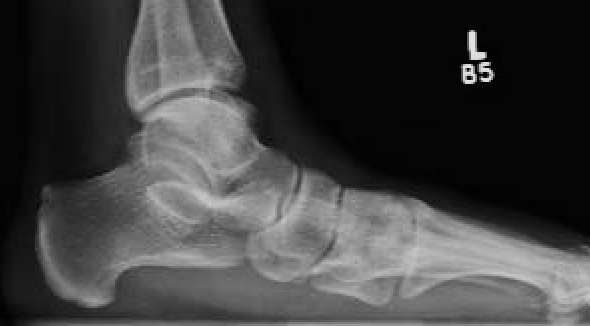

Lateral weight bearing

Early - reduced talo-metatarsal angle / Meary's angle

Late - subtalar joint OA